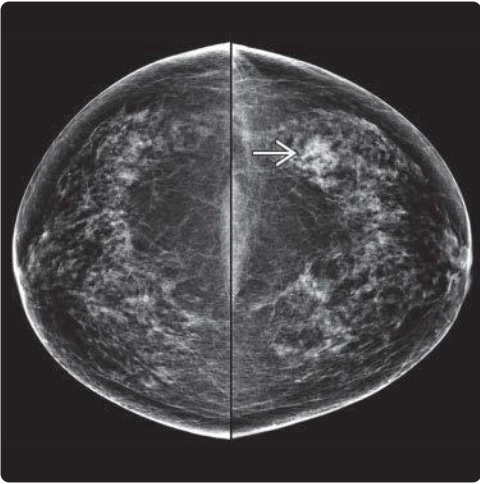

• Tuyến vú